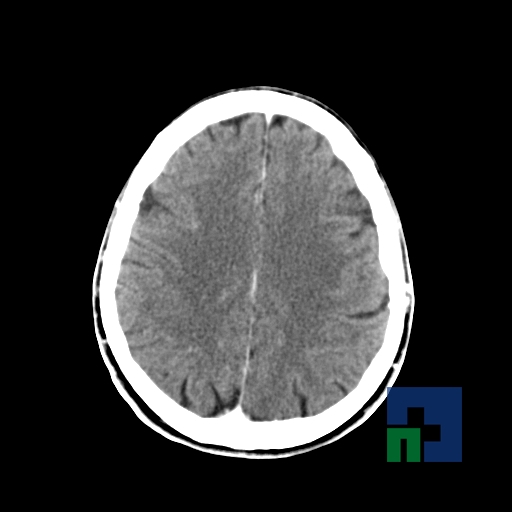

Examinare de rutină cerebrală, nativ și cu substanță de contrast (SDC) pentru diagnosticul:

- Accidentelor vasculare cerebrale ischemice sau hemoragice

- Tumorilor cerebrale

În cazul traumatismelor cranio-cerebrale:

- Evaluarea deplasării liniei mediane

- Evaluarea cisternelor perimezencefalice

- Diagnosticul edemului cerebral, a contuziei cerebrale, a leziunilor axonale difuze edematoase/hemoragice, a dilacerării cerebrale, a hematomului intraparenchimatos posttraumatic, a hematoamelor subdurale/extradurale (acute, subacute, cronice), a hemoragiei intraventriculare, a hemoragiei subarahnoidiene

- Diagnosticul traumatismelor de bază de craniu

- Diagnosticul fistulei LCR

- Diagnosticul herniilor cerebrale